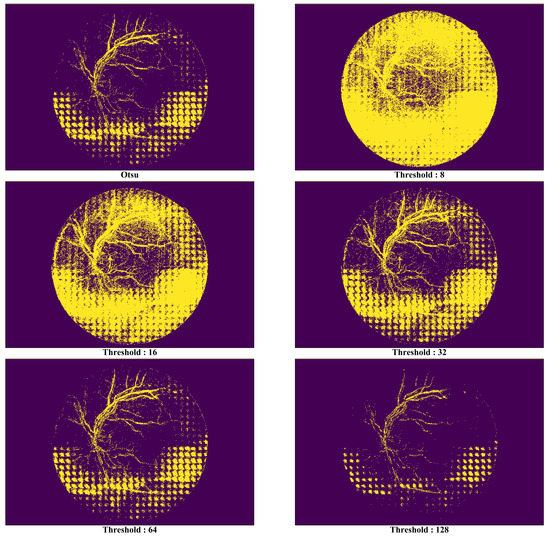

Figure 13. Comparison of synthetic vessel images by threshold types.

As the noise removal performance by the proposed technique can be affected by the threshold values used when defining a mask, we evaluated the noise removal performance of each threshold value to achieve the optimal noise removal performance level possible. Each pixel in an input image converted with a gray scale has 256 levels, indicating that the color would become darker as it approaches near 0 or vice versa. For the threshold function, all the pixels having a gray-scale level exceeding the parameter value were set to 255, whereas the opposite ones were set to 0. Figure 13 shows the masks generated from the six threshold types in the image in Figure 9. Since the area indicated as 1 (yellow section) due to the mask applied with a threshold type would import the pixel of a similar image, the mask that represents the area of the noise (i.e., the yellow section) more clearly will be deemed as a good mask.

In Figure 13, it is possible to know in the picture that there is no significant meaning in the areas distinguished by the mask as most their pixel values are 1 when the threshold value is 8. Although such a phenomenon had decreased when the threshold value was increased from 16 to 32, the areas that had been excessively identified as noise existed at the top of the image. The optimal performance was seen when the threshold value was 64, but it became harder to distinguish the noise areas as the value exceeded it.

For this study, the Otsu method [60,61,62,63,64,65,66,67,68,69] was applied to select reliably threshold value that has a great influence on the synthesized results of the proposed approach. The Otsu method provides the criteria for setting the most natural threshold value using a statistical method. This method defines two variances for a threshold value, T , which could be from 0 to 255.